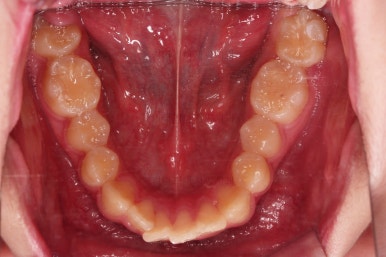

치료 끝!

전체적인 교정을 하지 않아끼 때문에, 완벽히 디테일을 맞추긴 힘들었지만 충분히 기능을 할 수 있게끔 위치를 바로잡아 주었어요.

총 치료기간은 단 5개월!

치료 전후 비교해 볼게요.

5개월이라는 매우 짧은 기간 안에 정확한 치료계획과 고난이도 테크닉으로 매복 사랑니도 발치하고 매복된 어금니도 바로 세워서 잘 사용할 수 있게끔 해드렸습니다.

이상 매복 사랑니를 발치하고 매복된 어금니를 살려쓴 부분교정 치료사례였습니다.